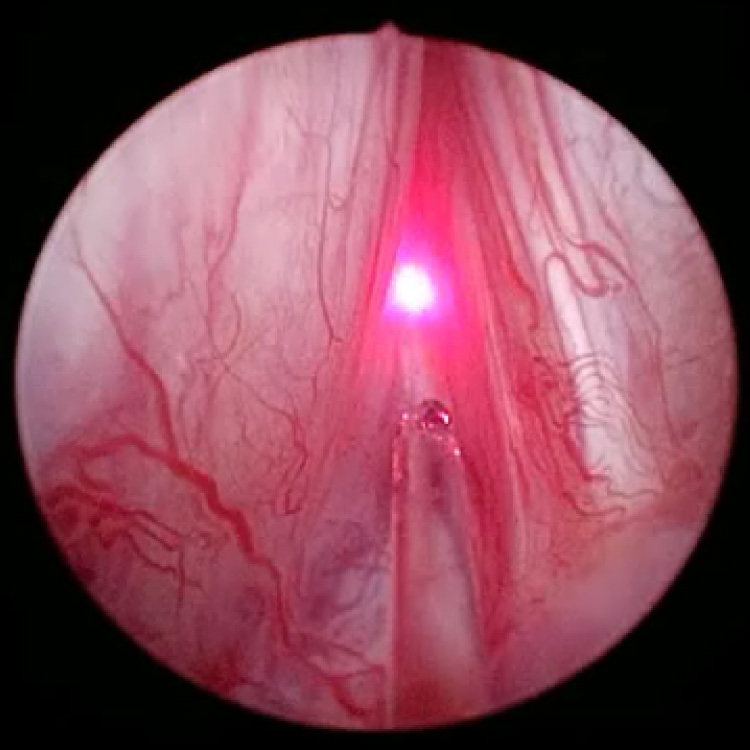

泌尿器科学会の推奨する尿路結石治療ガイドラインに準じて治療オプションの提示・決定を原則としています。尿路結石には体外衝撃波結石破砕術や内視鏡を使った手術を行っており、多くは通院治療で行っています。体外衝撃波では治療困難な症例に対しては内視鏡手術(経尿道的腎尿管砕石術)を施行します。ホルミウムレーザー砕石装置および細径内視鏡が導入されており、内視鏡手術の安全性と有効性が高くなっています。